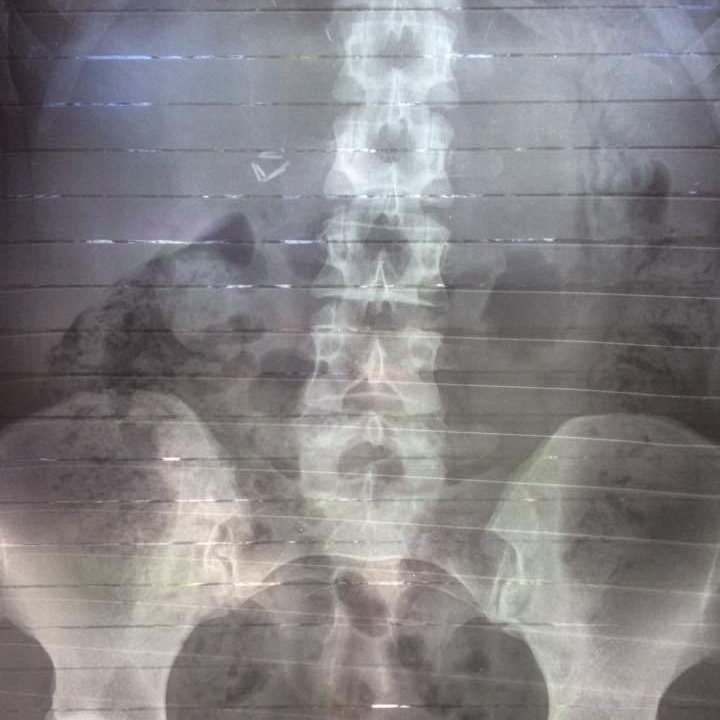

All the intrusive medical tests. Oh my god the endless tests.

Operations.

I carry titanium staples in my abdomen now.